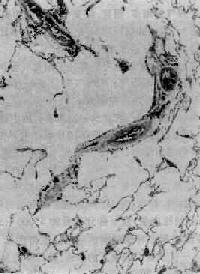

图9-10 慢性支气管炎 支气管粘膜纤毛上皮出现较多杯状细胞,部分呈磷状上皮化生